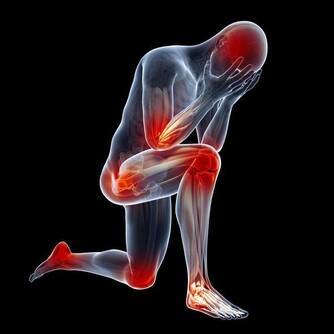

●冬天好發中風、心肌梗塞,邱正宏醫師還要傳授一套來自日本的"殭屍體操",只要原地搖擺身體,能幫血管放鬆,有助緩解肩頸痠痛!

●久坐的危害,等同抽兩根菸?!如何對抗久坐危機?脊骨神經醫學專家黃如玉,帶來秘密武器"健康呼拉椅",坐在椅子上,就像是搖呼拉圈!

●保命防"跌"有新招!職能治療師徐菁蕾要教大家一套"平衡木運動"!如何走路才正確?徐老師還要用拉筋器傳授一招"企鵝走路法"!

●小鮮肉教練,運動防護員黃健哲,還要教大家幾招"屁股造山運動",屁股練好,人不老,還能改善腰背膝蓋痛!精彩內容,千萬別錯過!